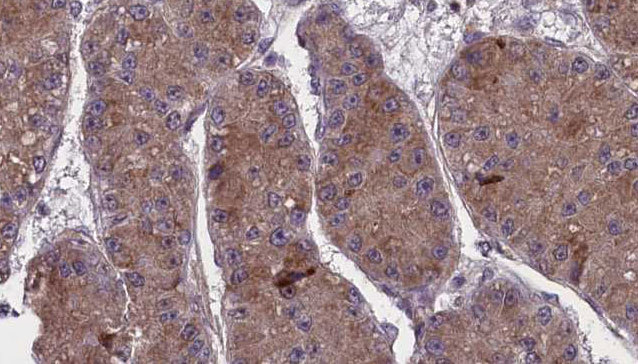

- Main image

- Experimental details

- 1:100 staining human liver carcinoma tissues by IHC-P. The sample was formaldehyde fixed and a heat mediated antigen retrieval step in citrate buffer was performed. The sample was then blocked and incubated with the antibody for 1.5 hours at 22°C. An HRP conjugated goat anti-rabbit antibody was used as the secondary.